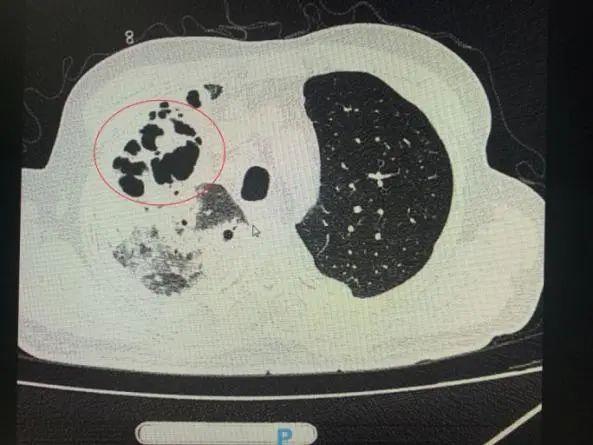

番禺院區(qū)呼吸內(nèi)科何夢(mèng)璋主任接診后,對(duì)鐘叔進(jìn)行詳細(xì)檢查。此時(shí),鐘叔的病情已經(jīng)十分危急,由于不能自主呼吸,他帶上了呼吸機(jī)輔助呼吸調(diào)節(jié)??吹界娛逍仄瑫r(shí),醫(yī)護(hù)人員頭皮也一陣發(fā)麻,胸部CT可見雙肺多發(fā)的炎癥浸潤(rùn)、雙肺多發(fā)空洞。通俗來說,鐘叔的肺部已經(jīng)被病原體蠶食,啃出個(gè)大小各異的洞!可怕的是,這種病變對(duì)肺功能的破壞是性、不可恢復(fù)的。根據(jù)鐘叔病史以及胸部CT結(jié)果,終診斷為“吸入性肺膿腫”。

鐘叔的肺部被病原體蠶食,啃出個(gè)大小各異的洞。